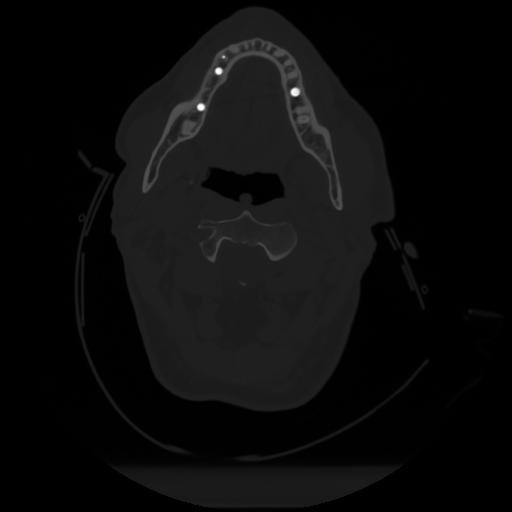

12 P.BLANDAS,,Vol,0.5,P.BLANDAS,,